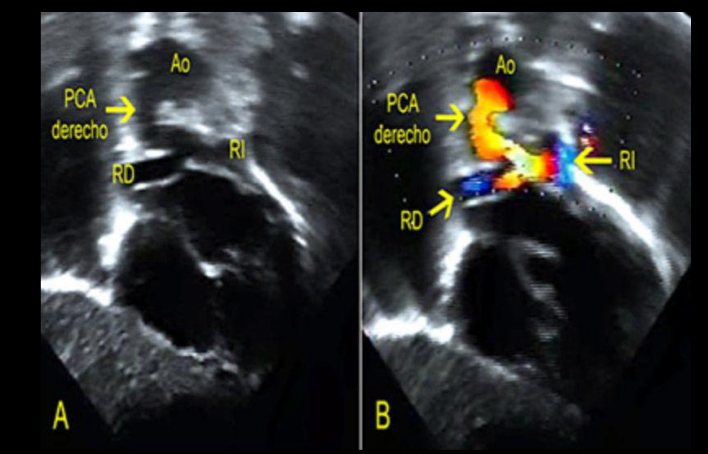

eco cardio